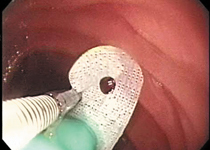

Wings are equipped on 2 parts on the tip of the ileus tube and 2 parts of its body and can be grasped by endoscopic biopsy forceps. Smooth procedures and reliable tube insertions are possible.

| Grasping the wing with forceps | Storing forceps | Advancing the ileus tube and passing the pylorus |